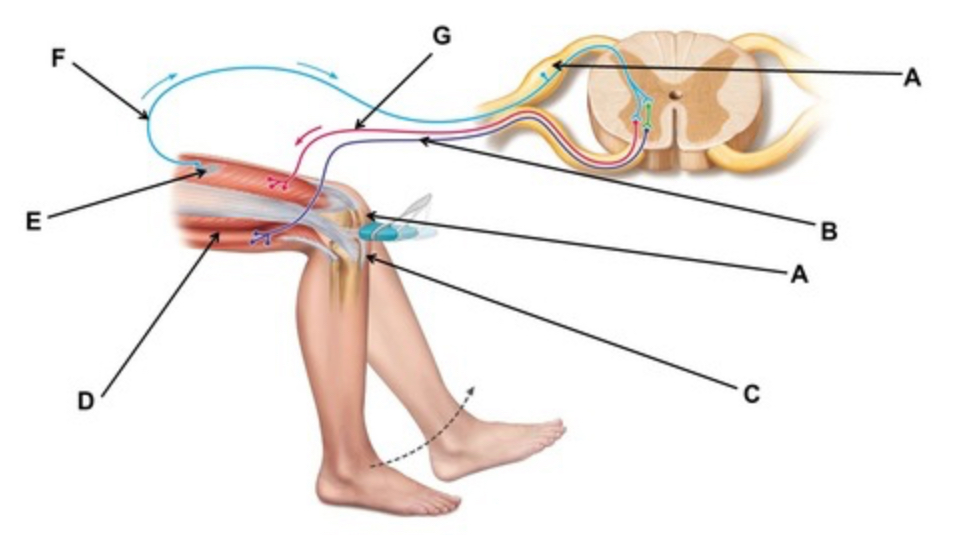

This test could be used to test the functioning of which peripheral nerve?

femoral

When conducting this reflex, which muscle(s) are inhibited?

hamstrings

When conducting this reflex, which muscle(s) contracts?

quadriceps

The crossed extensor reflex is an example of a(n) ________.

somatic reflex